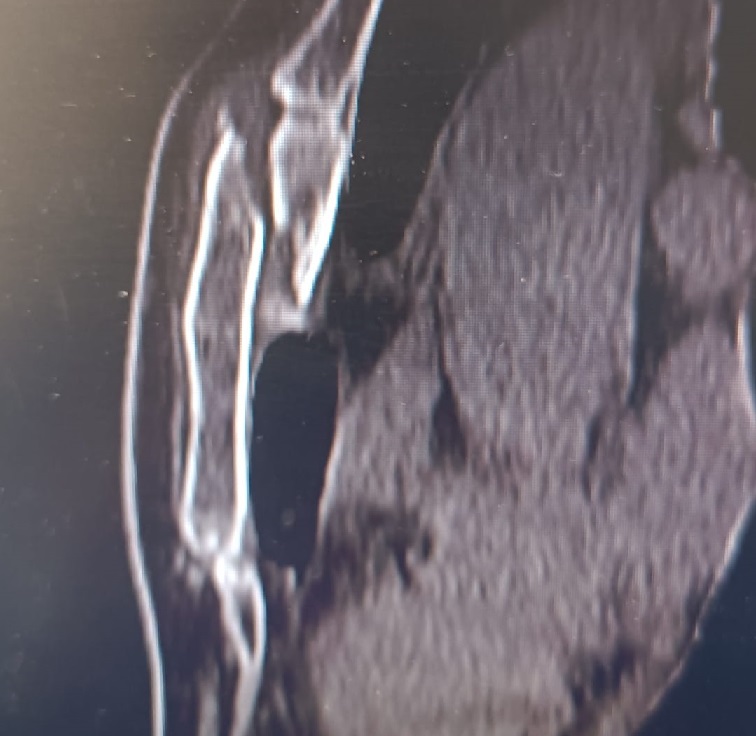

• Tomografia Computerizzata del Torace (TC Torace): utile per valutare meglio la gravità della frattura e le eventuali lesioni associate (Figura 1);

Tomografia Computerizzata del Torace: ricostruzione sagittale che mostra una frattura scomposta dello sterno con monconi sovrapposti

Figura 1 - Tomografia Computerizzata del Torace: ricostruzione sagittale che mostra una frattura scomposta dello sterno con monconi sovrapposti